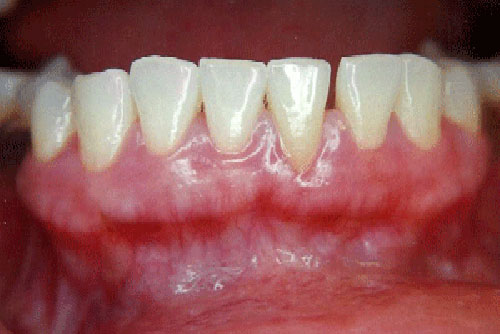

Treatment of dark/pigmented gums - Gingival depigmentation

Gingival Depigmentation